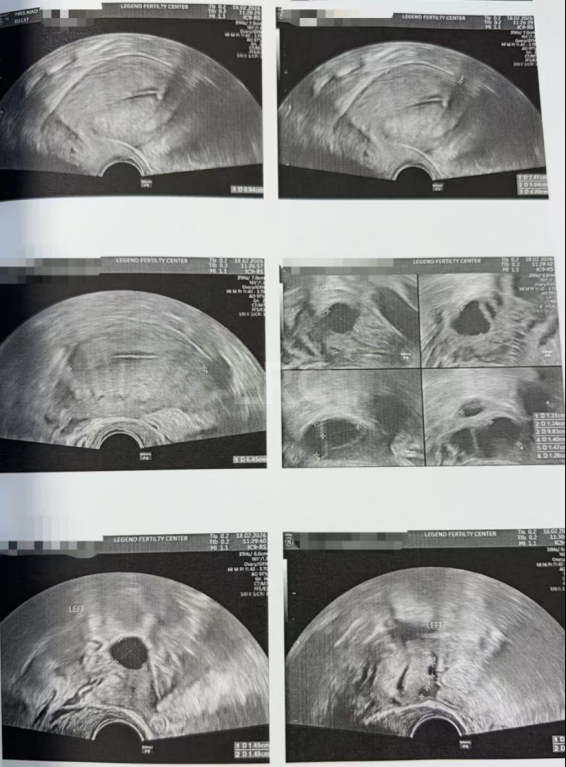

针对 X 女士夫妇的核心生育问题,颂宝医生团队摒弃常规标准化促排方案,量身定制了精细化促排方案 + 专属身体调理方案,全程动态监测阴超和激素水平,实时把控卵泡发育节奏,根据每一次的监测结果调整诊疗策略,确保有限的卵泡资源实现最大化、最优质的发育,具体促排监测过程如下:

月经第二天 促排第一天

阴超检查:基础卵泡 8 颗

- 右侧卵泡 7-8 颗 (2-10mm)

- 左侧卵泡 0 颗 (-mm)

促排第四天

阴超检查:

- 右侧卵泡 5-6 颗 (-mm)

- 左侧卵泡 4-5 颗 (-mm)

促排第五天

- 右侧卵泡 6 颗 (13,11,10,9,9,5mm)

- 左侧卵泡 2 颗 (10,9,4mm)

促排第八天

- 右侧卵泡 5 颗 (17,16,14,13,12mm)

- 左侧卵泡 1 颗 (15mm)

促排第十天

- 右侧卵泡 5 颗 (23,19,18,17,17,10mm)

- 左侧卵泡 1 颗 (16mm)